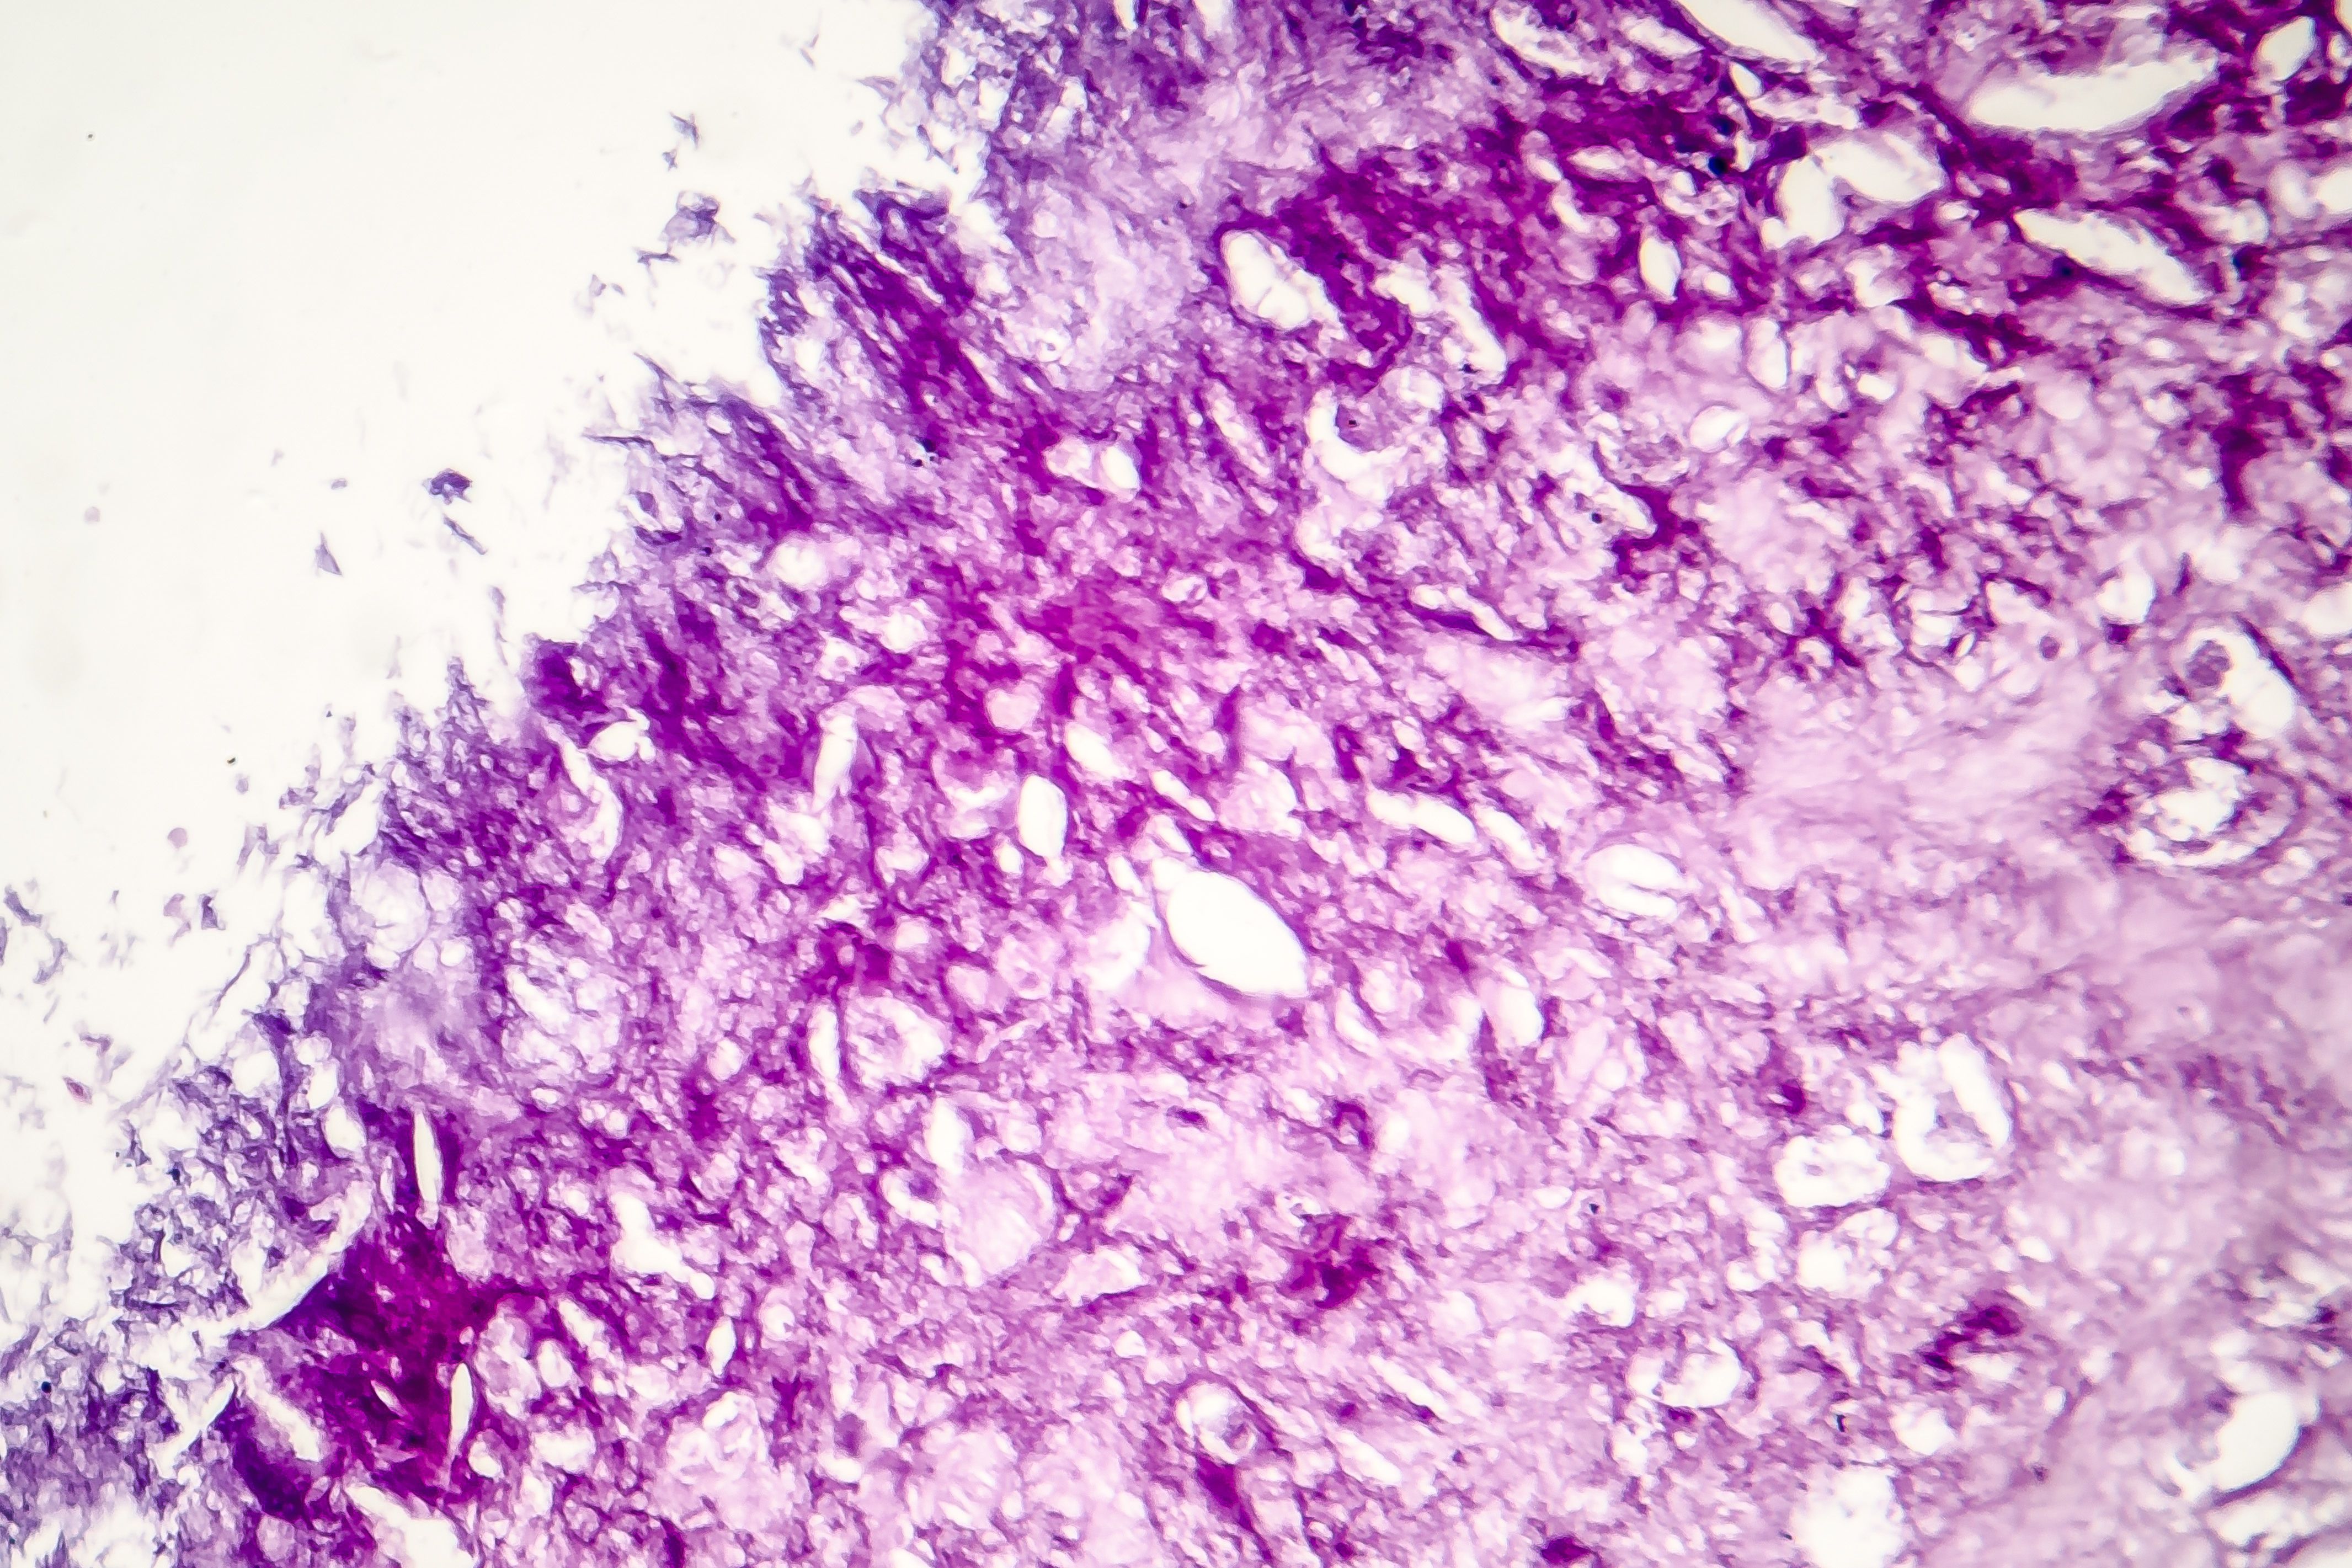

A 79-year-old white man presented with an ulcerated chest wall lesion developing from an existing mole.